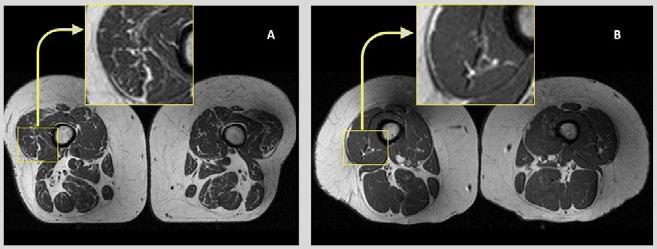

Eating Ultra-Processed Foods Impacts Muscle Quality

Adiet high in ultra-processed foods is associated with higher amounts of fat stored inside thigh muscles, regardless of the amount of calories consumed or level of physical activity, according to a study presented by a team of UCSF researchers at the 2024 RSNA meeting. Higher amounts of intramuscular fat in the thigh could also increase the risk for knee osteoarthritis.

“The novelty of this study is that it investigates the impact of diet quality, specifically the role of ultra-processed foods in relation to intramuscular fat in the thigh muscles assessed by MRI,” said author Zehra Akkaya, MD, researcher and former Fulbright Scholar in the Department of Radiology and Biomedical Imaging at the University of California, San Francisco. “This is the first imaging study looking into the relationship between MRI-based skeletal muscle quality and quality of diet.”

“Research from our group and others has previously shown that quantitative and functional decline in thigh muscles is potentially associated with onset and progression of knee osteoarthritis,” Dr. Akkaya said. “On MRI images, this decline can be seen as fatty degeneration of the muscle, where streaks of fat replace muscle fibers.”

Figure 1. Axial T1-weighted bilateral thigh MR images and magnified frames providing a closer look at the areas in lateral aspects of quadriceps femoris muscles (knee extensors) from two obese, female participants, aged 58 (A) and 62 years (B), respectively. In A, the thigh muscles on both sides demonstrate abundant fatty streaks, consistent with a high Goutallier grade of 45 for this participant, whose diet from the past 12 months consisted 68% of ultra-processed foods. In B, the thigh muscles show fewer fatty streaks as highlighted in the magnified image, consistent with a low Goutallier grade of 17 for this participant, whose diet contained only 36% ultra-processed foods.

The researchers found that the more ultra-processed foods people consumed, the more intramuscular fat they had in their thigh muscles, regardless of energy (caloric) intake.

“In an adult population at risk for but without knee or hip osteoarthritis, consuming ultra-processed foods is linked to increased fat within the thigh muscles,” Dr. Akkaya said. “These findings held true regardless of dietary energy content, BMI, sociodemographic factors or physical activity levels.”